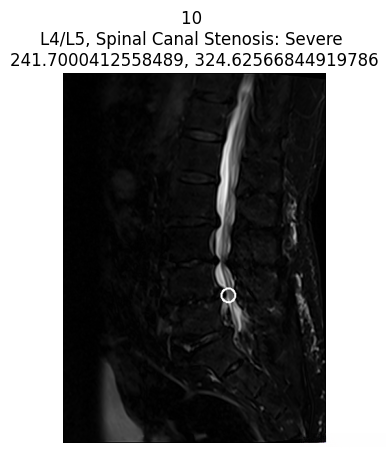

查看病变的坐标

我们还可以显示每位患者标注的病变坐标。

coor_entries = df_coor[df_coor['study_id'] == int(patient['study_id'])]

print("Only showing severe cases for this patient")

for idc, c in coor_entries.iterrows():

for i in im_list_dcm[str(c['series_id'])]['images']:

if int(i['SOPInstanceUID']) == int(c['instance_number']):

try:

patient_severity = patient[

f"{c['condition'].lower().replace(' ', '_')}_{c['level'].lower().replace('/', '_')}"

]

except Exception as e:

patient_severity = "unknown severity"

title = f"{i['SOPInstanceUID']} \n{c['level']}, {c['condition']}: {patient_severity} \n{c['x']}, {c['y']}"

if patient_severity == 'Severe':

display_coor_on_img(c, i, title)

AI写代码

仅显示该患者的严重病例